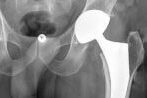

Prothèses totales de hanche, PTH

Reprise de PTH